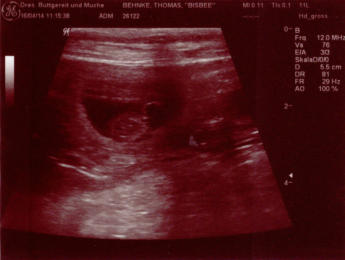

Mittwoch, 16. April 2014 Der Besuch beim Tierarzt brachte Licht ins Dunkel und die Bestätigung.        - Bisbee ist trächtig. -   Der Tierarzt konnte einiges an Gewusel sehen, aber eine genaue Anzahl ist natürlich noch nicht erkennbar. Wir lassen uns überraschen was am Ende rauskommt.  Die Vorbereitungen für unseren A-Wurf können also weiter gehen. Der Termin ist ca. der 21. Mai 2014.